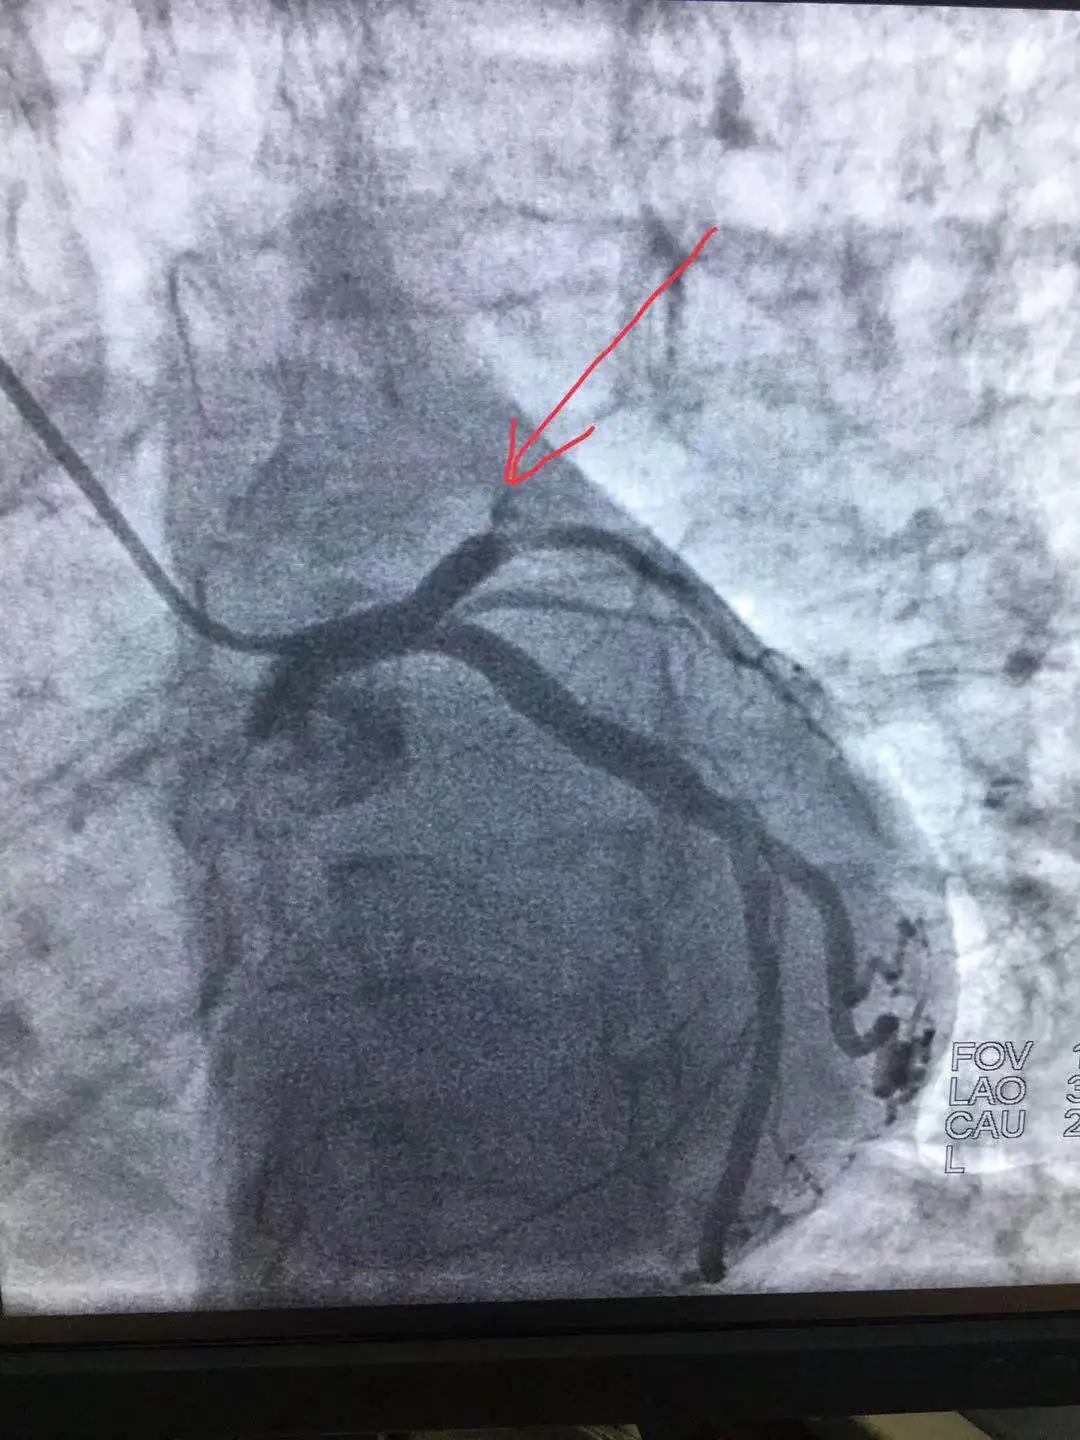

心內(nèi)科醫(yī)務人員冠狀動脈造影中

“冠狀動脈造影”即“冠脈造影”,是診斷冠心病的一種常用方法,作為一種有創(chuàng)診斷技術,它被稱為診斷冠心病的“金標準”。心內(nèi)科融無創(chuàng)與有創(chuàng)協(xié)同治療為一體,硬件設施齊全,配有美國GE大C型臂數(shù)字減影X線造影機,心臟臨時起搏器、床旁監(jiān)護儀、除顫儀、自動分析心電圖等,設有心臟重癥監(jiān)護室(CCU),擁有1個獨立導管室,設有心內(nèi)科??崎T診、心內(nèi)科病房(現(xiàn)有床位71張)、心血管無創(chuàng)檢查室、心電圖室等部門。科室現(xiàn)已熟練開展冠狀動脈造影技術,為心血管疾病患者帶來了福音。

冠狀動脈內(nèi)支架植入術是目前治療冠心病的最有效的方法之一。不用開刀,其緩解癥狀的作用迅速可靠。對于藥物治療效果差,經(jīng)選擇性冠狀動脈造影明確冠狀動脈有局限性或階段性狹窄的患者,通過冠狀動脈內(nèi)支架植入術,使血管狹窄處的血流恢復正常,有效保證心肌的血液供應,緩解病人的臨床癥狀,提高病人的生活質(zhì)量。